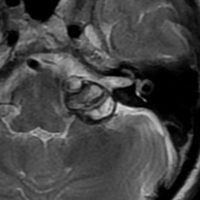

脳幹部の海綿状血管腫 brainstem cavernous hemangioma

2度の延髄内出血を生じた海綿状血管腫です。でも初回の出血からすでに27年間がたちます。症状も回復して麻痺もなくていまは社会生活に困ることはありません。脳幹部の海綿状血管腫の中には1ヶ月に何回もひどい出血を繰り返すのもあるのですが,この例のように30年近い間に軽い出血が2回だけというのもあります。残念ながら正確にこれを予測することはできません。この患者さんの海綿状血管腫は手術で摘出すれば麻痺などの合併症の可能性があるのでしません。

脳幹部の海綿状血管腫を手術した方がいいかどうかはすごく慎重に判断しないといけないのです。場合によってはとても重い後遺症が手術ででてしまうこともあります。もちろん手術ですごく症状がよくなってとても元気に暮らしている患者さんもたくさんいますが,そうでない患者さんもいるのです。手術を決意する前に,少なくとももう一人の脳外科医からセカンドオピニオンを聞きましょう。